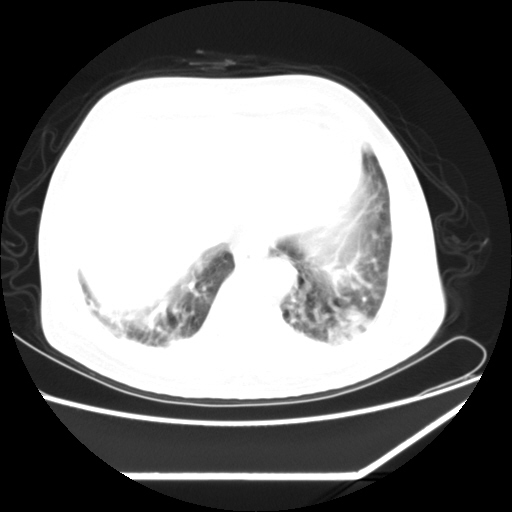

男,57,畏寒,发热

两侧多发肺脓肿,两侧胸膜增厚,抗炎治疗后复查

双肺多发结节样病灶,部分内见透光区,纵隔内见淋巴结肿大。结核临床如有畏寒,高热,白细胞增高首先考虑迁徙性肺脓肿(多是金黄色葡萄球菌感染)。

畏寒发热,首先考虑血源性肺脓肿,结合临床,抗炎后复查排除转移瘤等。

1)考虑两肺感染性病变(金黄色葡萄球菌肺炎?);建议抗炎治疗后复查排除其他。2)双侧少量胸腔积液。